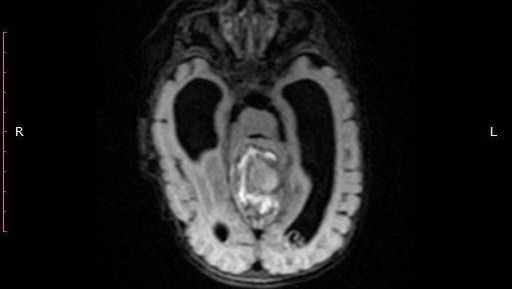

Ещё один важный прорыв башкирских хирургов – они смогли удалить злокачественную опухоль мозга двухмесячному малышу. Уникальную операцию провели в Республиканской детской клинической больнице. Ребенка экстренно доставили в Уфу санавиацией из Баймакского района. Состояние малыша ухудшалось на глазах. Маленького пациента беспокоили частые рвотные позывы, наблюдался непропорциональный рост головы. В больнице поставили неутешительный диагноз – опухоль мозга. Ребенку провели двухэтапную высокотехнологичную операцию: нейрохирурги удалили опухоль и убрали сопутствующий застой жидкости. Операционный материал отправили в ведущую детскую онкологическую клинику страны. Там подтвердили злокачественную природу опухоли. Поэтому дальше малыша лечили уже в Москве.